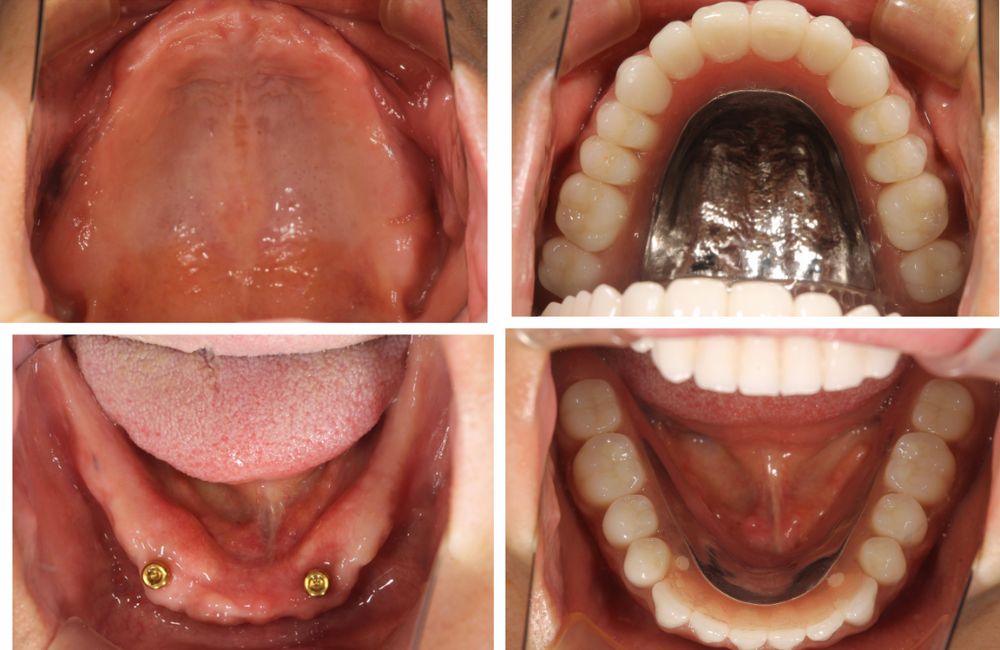

初診時の口腔内写真

インプラントオーバーデンチャーの装着前と装着後